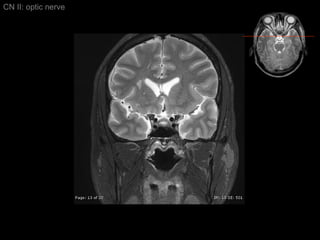

CN II: optic nerve Axial T2/ inferior to superior

CN II: opticnerve Axial T2/ inferior to superior